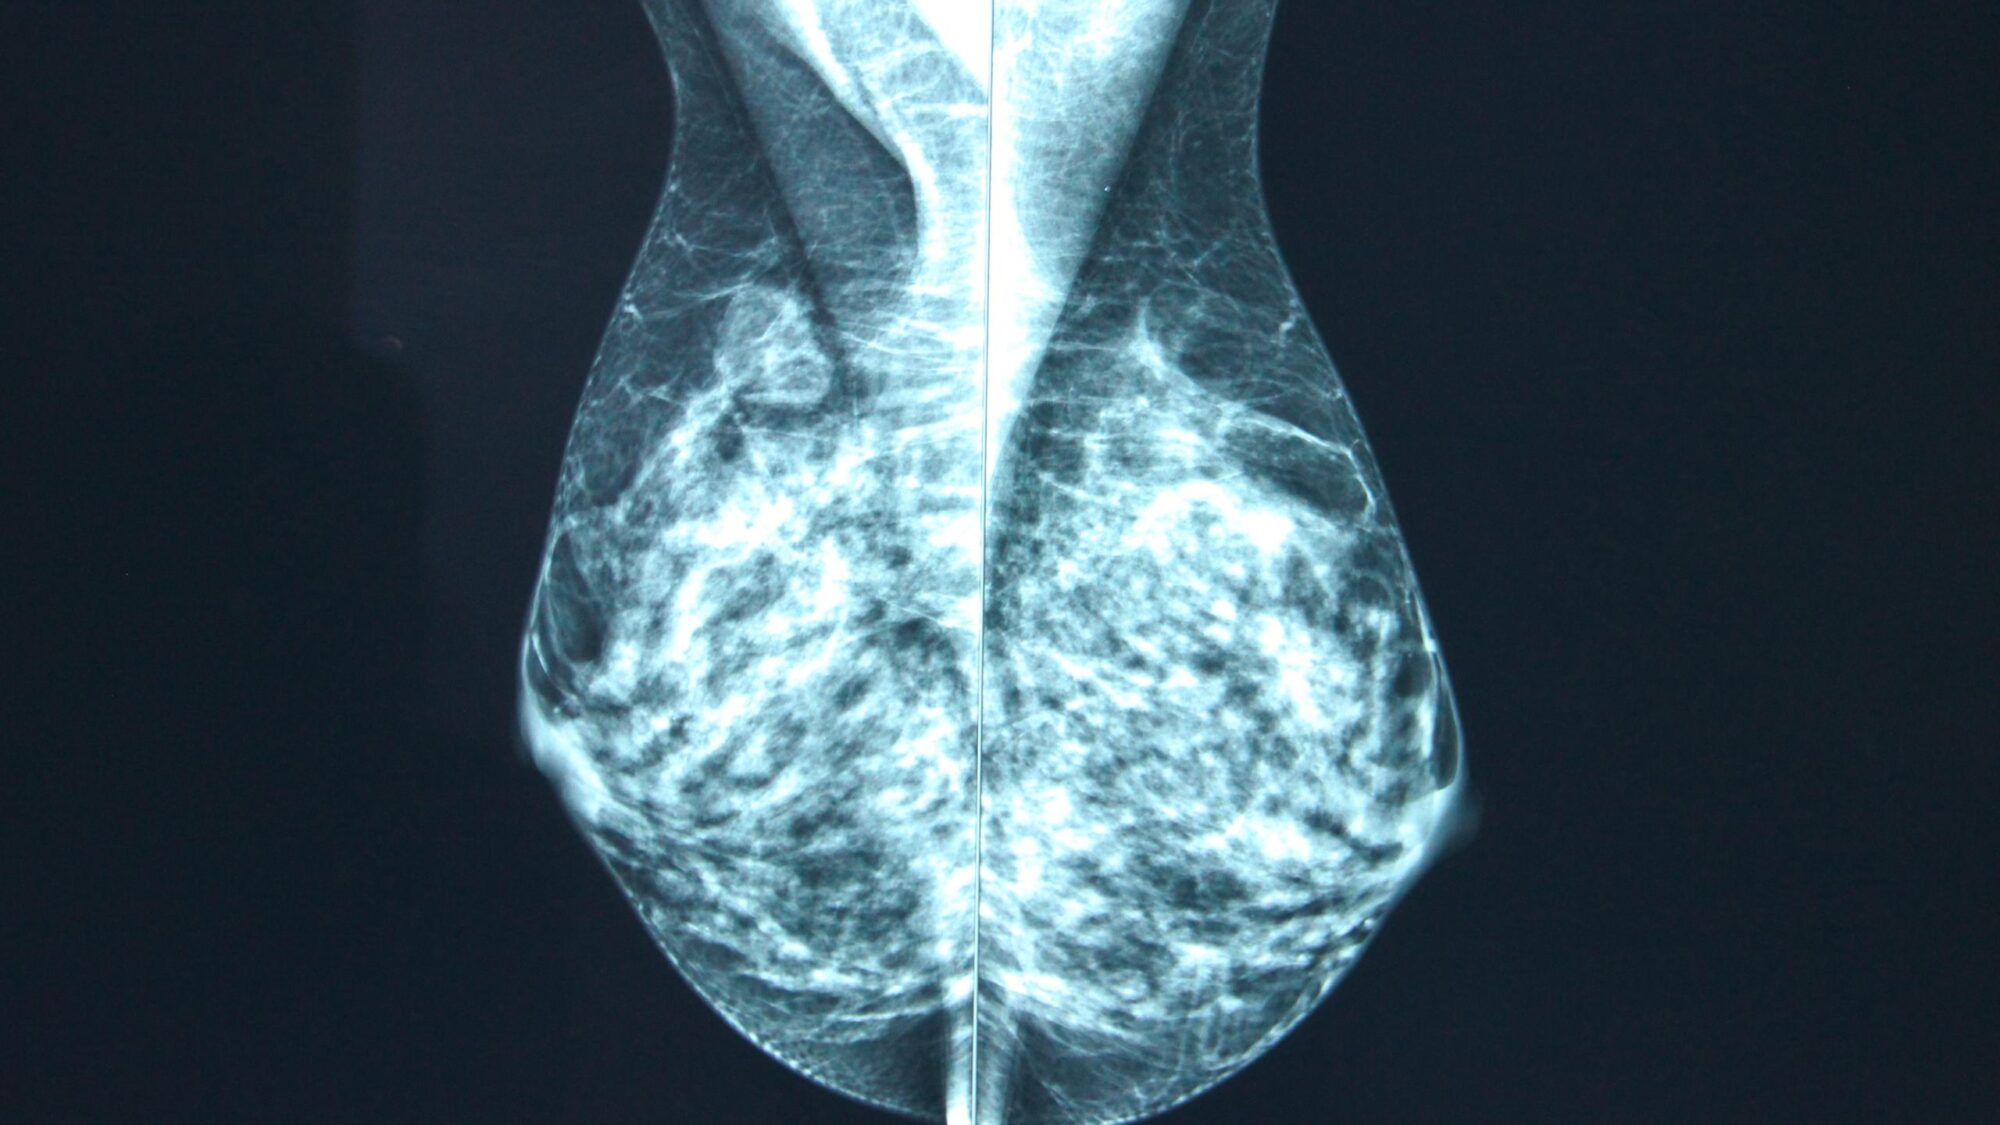

En 2022, des chercheurs de l’université de Münster (Allemagne) avaient réalisé l’essai randomisé TOmosynthesis plus SYnthesized MAmmography (TOSYMA), qui concluait que le taux de détection du cancer du sein invasif était significativement plus élevé avec la tomosynthèse mammaire associée à la mammographie 2D synthétique qu'avec la mammographie numérique seule. En 2025, la même équipe a publié les résultats d’une sous-analyse de l’essai TOSYMA qui ciblait plus particulièrement les femmes aux seins denses [1].

Dans cette étude, les chercheurs allemands ont comparé la dose glandulaire moyenne chez les femmes des deux bras de l'essai, classées selon les catégories de densité mammaire, et l’ont mise en relation avec les taux de détection des cancers du sein invasifs. Au total, 196 622 expositions provenant de 49 227 femmes du groupe "tomosynthèse + mammographie synthétique", et 197 037 expositions provenant de 49 132 femmes du groupe témoin "mammographie seule" ont été